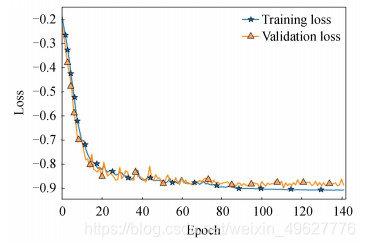

图 9和10分别为结合实例归一化网络收敛示意图和脑肿瘤测试集Dice指标分布图.对比图 7(b)和图 9可知,结合了实列归一化的脑肿瘤检测网络收敛速度更快,训练集和测试集的损失值曲线拟合程度良好,表明实列归一化的方法不仅能够加快网络的收敛速度,同时也缓解了多模态脑肿瘤检测网络中存在的过拟合问题.

图 9 结合实例归一化网络收敛示意图

从图 11可知,结合实例归一化的方法其脑肿瘤检测网络的三种评价指标Dice、SN和SE可以达到0.881 8、0.893 5和0.996 9,较3.2.1节中的多模态脑肿瘤检测模型,Dice、SN两项指标各提升了3.92%和6.81%,而SE指标降低了0.02%.

对比图 16和12可知,三维检测网络的损失函数收敛拟合程度更佳,二维检测网络的训练和测试损失值为-0.875 9及-0.870 7,而三维检测网络可达到-0.909 4和-0.901 7,分别提升了3.35%和3.1%.